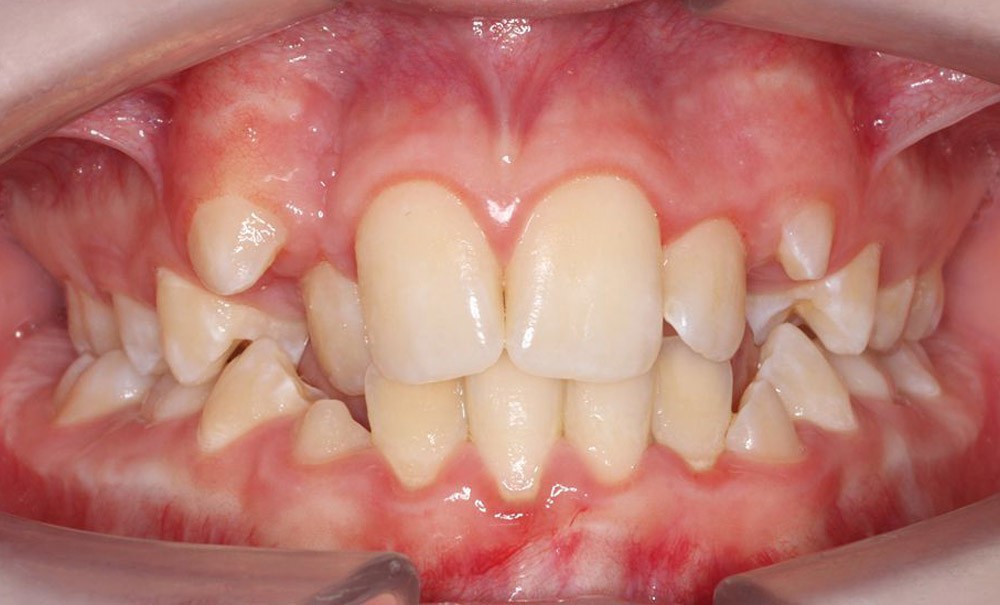

En avril de cette année 2025, Nathan1 est venu consulter accompagné de sa mère, sur les recommandations de son pédiatre et de son neurologue spécialiste du sommeil. Une polysomnographie réalisée en janvier de cette même année avait révélé une Index d’Apnées Hypopnées Obstructives (IAHO) de 39,6, une valeur très sévère pour un enfant. À la suite de cet examen, ce jeune patient de 12 ans a été opéré en mars en urgence, avec une ablation des végétations et des amygdales. Après l’intervention, son score de la somnolence dans la journée est passé de 16 à 10 selon l’échelle de Somnolence d’Epworth2 [1]. Lors de ce premier rendez-vous en vue d’un traitement d’orthodontie, l’examen clinique a mis en évidence une Classe I molaire, une ectopie des 13 et 23 associée à une déviation des médianes incisives ainsi qu’une dysharmonie dentoalvéolaire modérée. Il n’y avait pas d’occlusion inversée des secteurs latéraux, mais le palais était profond et la typologie faciale hyperdivergente (fig. 1). Une expansion maxillaire rapide (EMR) a été programmée en avril avec une activation matin et soir pendant 15 jours. Ainsi, 6 millimètres d’expansion transversale ont été obtenus. Un…